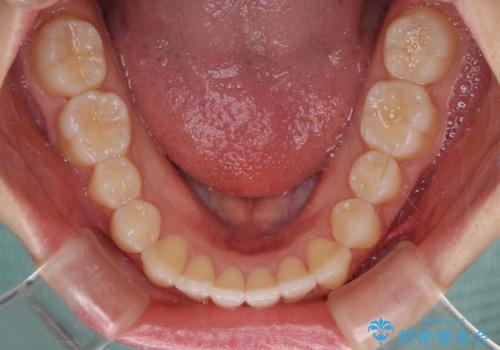

前歯のクロスバイト インビザラインによる矯正治療

- 前歯のクロスバイトを気にして来院された患者様です。

短期間での治療を希望され、ワイヤー装置とインビザラインとで悩んでいましたが、自己管理を徹底すると言うことでインビザラインによる矯正治療を行うこととしました。

しっかりとインビザラインの装着時間を守っていただいたので、1年弱で矯正治療を終えることができました。